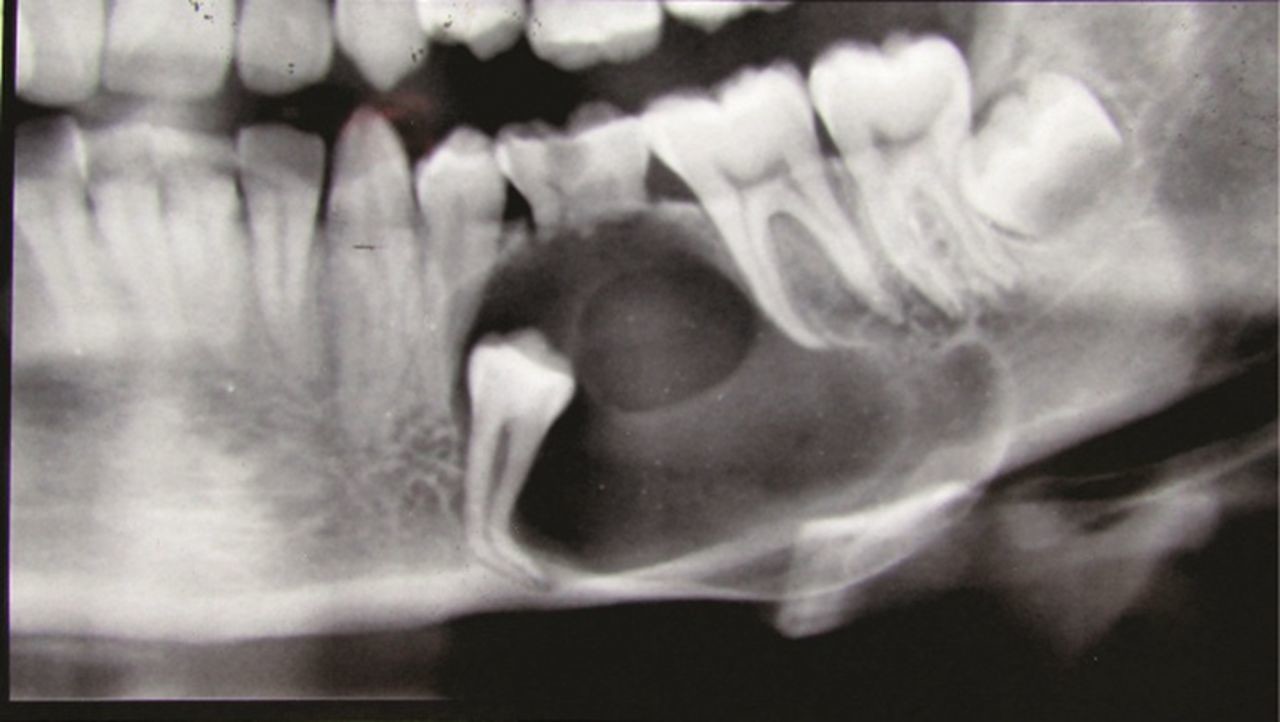

What is a dentigerous cyst?

Dentigerous cysts are the second most common type of odontogenic cyst, which is a fluid-filled sac that develops in the jaw bone and soft tissue. They form over the top of an unerupted tooth, or partially erupted tooth, usually one of your molars or canines. While dentigerous cysts are benign, they can lead to complications, such as infection, if left untreated.

What are the symptoms?

Smaller dentigerous cysts might not cause any symptoms. However, if the cyst grows larger than 2 centimeters in diameter, you may notice:

swelling

tooth sensitivity

tooth displacement

If you look inside your mouth, you may also notice a small bump. If the cyst causes tooth displacement, you might also see gaps slowly forming between your teeth.

How is it diagnosed?

Small dentigerous cysts often go unnoticed until you have a dental X-ray. If your dentist notices an unusual spot on your dental X-ray, they may use a CT scan or MRI scan to make sure it’s not another type of cyst, such as a periapical cyst or an aneurysmal bone cyst.

In some cases, including when the cyst is larger, your dentist may be able to diagnose a dentigerous cyst just by looking at it.

How is it treated?

Treating a dentigerous cyst depends on its size. If it’s small, your dentist might be able to surgically remove it along with the affected tooth. In other cases, they might use a technique called marsupialization.

Marsupialization involves cutting open the cyst so it can drain. Once the fluid has drained, stitches are added to the edges of the incision to keep it open, which prevents another cyst from growing there.